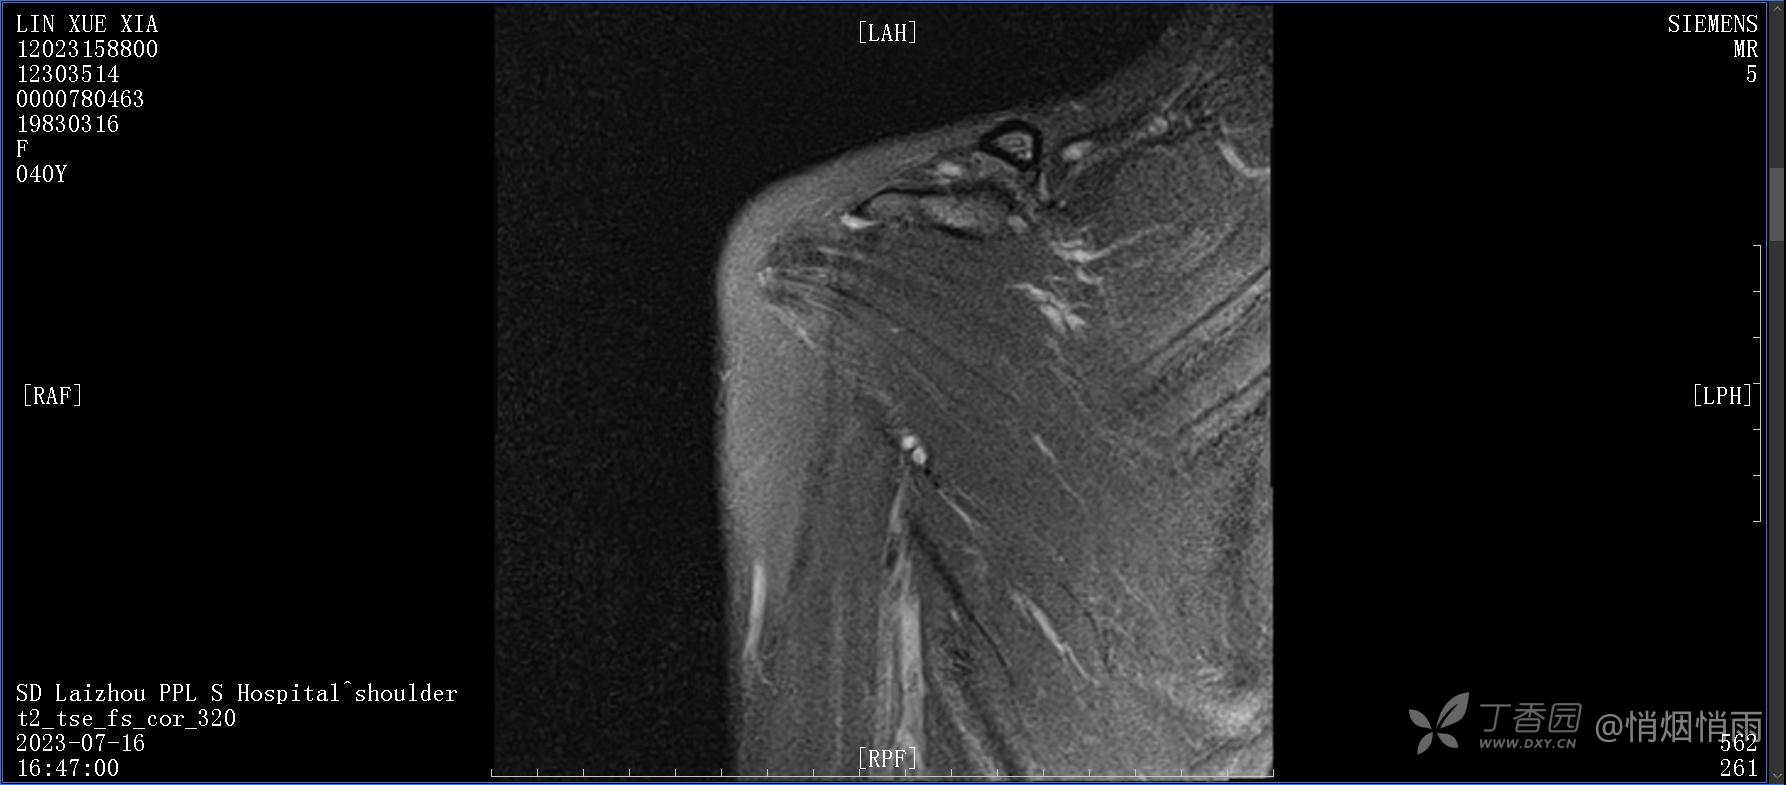

查体:右肩关节局部轻度肿胀,肩胛区压痛明显,痛处不固定,肩关节痛性活动受限,jobe test(+),lift -off test(+),中指、环指感觉较余指减退,余肢端感觉及血运情况可。

目前的诊断,暂时依据辅助检查诊为肩袖损伤,但是患者疼痛的性质和特点,却不是单纯的肩袖损伤所致。考虑过胸廓出口综合征,但是该疾病会出现肩胛区的疼痛吗?(由于考虑到费用的问题,没再进行下一步的检查)带状疱疹会有如此的症状吗?